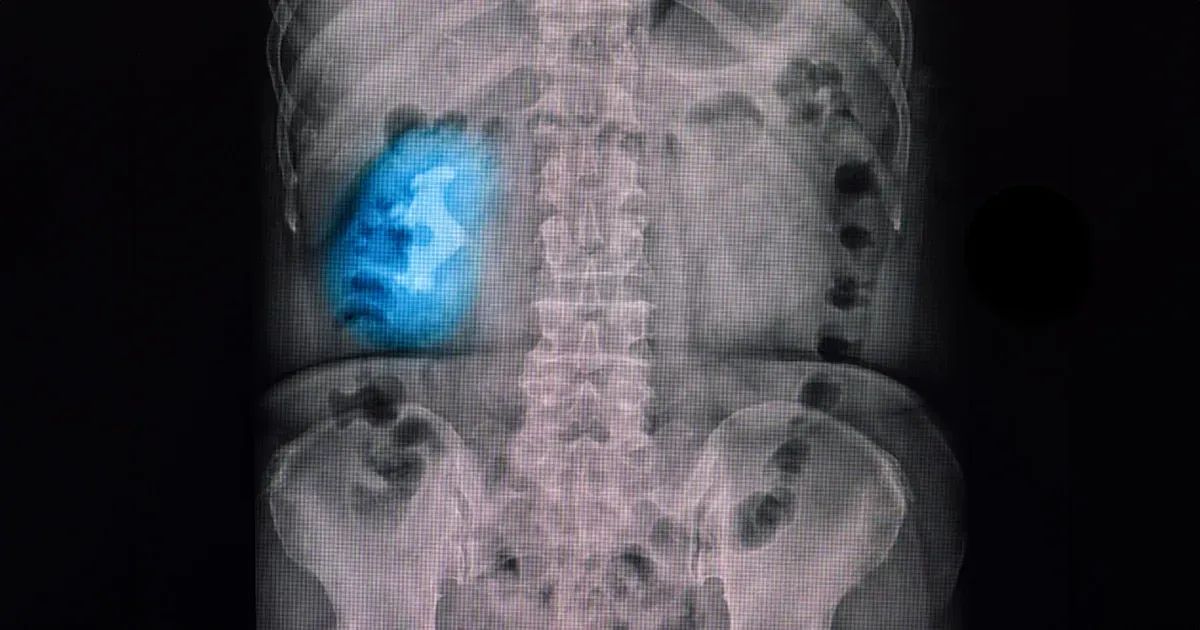

في أربع أنواع أساسية من حصى الكلى — أوكسالات الكالسيوم، حمض اليوريك، ستروفايت، والسيستين. من بين هذي الأنواع، حصى الستروفايت شكلها مميز أكثر، لأنها تكبر وتصير على هيئة فروع كبيرة يسمونها "حصى قرون الغزال"، تملأ الفراغات داخل الكلية.

حصى قرون الغزال، اللي سموها كذا لأن شكلها يشبه قرون الغزال، مكونة أساساً من الستروفايت (فوسفات المغنيسيوم الأمونيوم)، وعادةً تطلع بسبب التهابات المسالك البولية المزمنة، خصوصاً من بكتيريا تنتج إنزيم اسمه يورياز، مثل "بروتيوس ميرابيليس". هذا الإنزيم يكسر اليوريا، ويرفع نسبة الأمونيا في البول، ويزيد الـ pH، ويسوي بيئة قلوية تساعد على تكوين الحصى.

تشريح حصوات قرن الغزال يعقّد العلاج. هالحصوات تتفرع داخل الحوض الكلوي، وهو منطقة بالكلية شكلها قمعي توجّه البول للحالبين، اللي بدورهم ينقلونه للمثانة عشان يتخزّن. إذا انسدّ الحوض الكلوي أو الحالبين، راح يحدث تورّم في الكلية. هالحصوات ممكن كمان تسدّ الكؤوس الكلوية، اللي يبدأ منها تجمّع البول. تورّم هالمناطق، اللي يسمّى "توسّع الكؤوس"، إذا ما عولج راح يؤدّي لفشل كلوي، فالتشخيص والعلاج بسرعة ضروري.

الجمع بين هالاضطرابات الأيضية مع عادات غذائية سيئة أو جفاف يزيد فرصة تكوّن الحصوات. يتضمن تحليل البول والتصوير لتقييم وجود الحصوات والالتهابات. تحليل البول يفحص وجود البكتيريا وارتفاع مستوى الحموضة، اللي تدلّ على حصوات ناتجة عن التهابات. التصوير بالأشعة السينية أو الموجات فوق الصوتية أو الأشعة المقطعية يوضّح شكل الحصوة وحجمها ومكانها بالكلية.